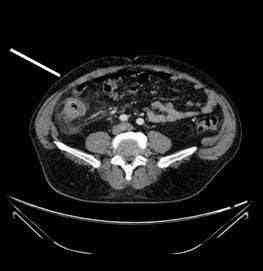

Figura 1: Imágenes radiológicas de la TC del paciente del CASO 1, donde se observan divertículos en colon ascendente cerca de ciego con inflamación de su pared y de la grasa adyacente. (Señalada con flecha blanca)

decide realizar una TC que visualiza engrosamiento de la pared de colon en ángulo hepático, con imágenes compatibles con divertículos en dicho punto e inflamación de la grasa pericolónica. La paciente es tratada de forma conservadora con antibioterapia intravenosa (imipenen) durante 5 días continuando la pauta antibiótica vía oral de forma ambulatoria con metronidazol y levofloxacino. Al mes y medio del proceso agudo inicial, la paciente acudió de nuevo al